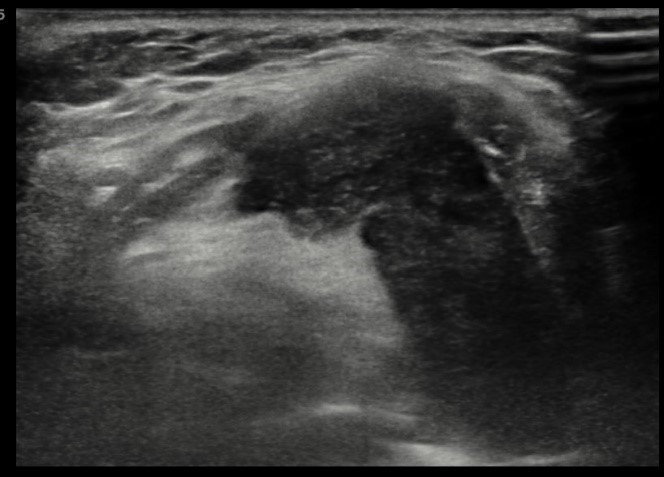

![]() |

Figure 5. Transverse image |